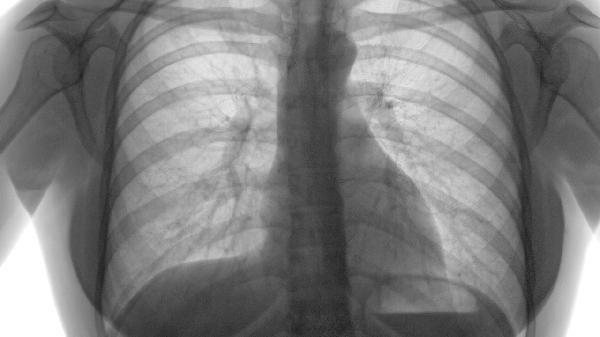

肺气肿可能由长期吸烟、空气污染、职业粉尘接触、遗传性α-1抗胰蛋白酶缺乏等原因引起,需通过肺功能检查、胸部影像学...